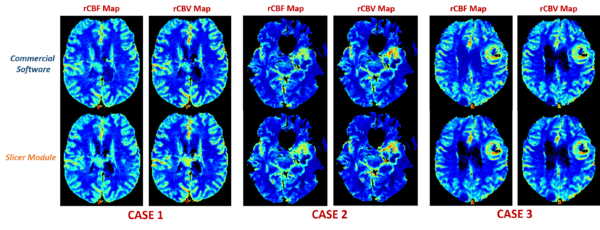

Comparison with the Commercial Software

• Compare the results with the outputs from existing commercial softwares